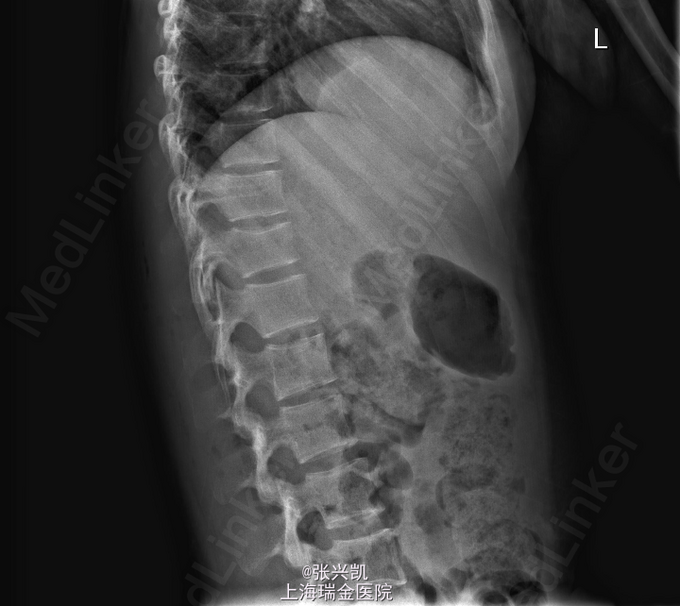

诊断:多发胸腰椎骨折(T11,L1) 处理:胸腰椎骨折经皮椎弓根钉复位内固定术,一年后骨折愈合良好,行内固定装置取出术

随访:术后三月复诊,内固定装置位置良好,患者腰背痛症状缓解,一年后骨折愈合,行内固定装置取出。术后患者腰部活动良好 讨论:术后应积极锻炼腰背部肌肉,防止萎缩。